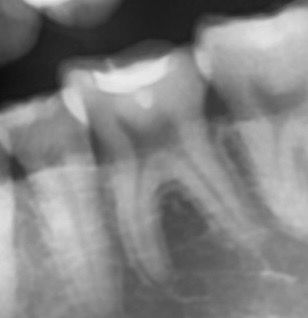

어금니 인레이 치료를 받았습니다 (아래 왼쪽 뒤에서 두번째 어금니)

1년동안 탈없이 잘 사용했는데 며칠전부터 자꾸 치아가 시립니다 가만히 있을때에도 은은하게 시리고 식사할때도 은은하게 시리는데 막 아프다 정도는 아닙니다

다만 잘못되었을까 걱정되네요 치아가 시리기전에 치과 검진을 갔었는데 (3주전) 그때는 별말씀 없으셨습니다.. 왜 시린건가요?.. 충치가생긴걸까요 아니면 인레이 틈이생긴걸까요?

컨디션이 안좋으면 며칠 일시적으로 그럴순 있습니다 일단 지켜보시고 증상이 심해지면 다시 치과 가보세요 지금 사진상으론 별다른 문제가 보이진 않습니다